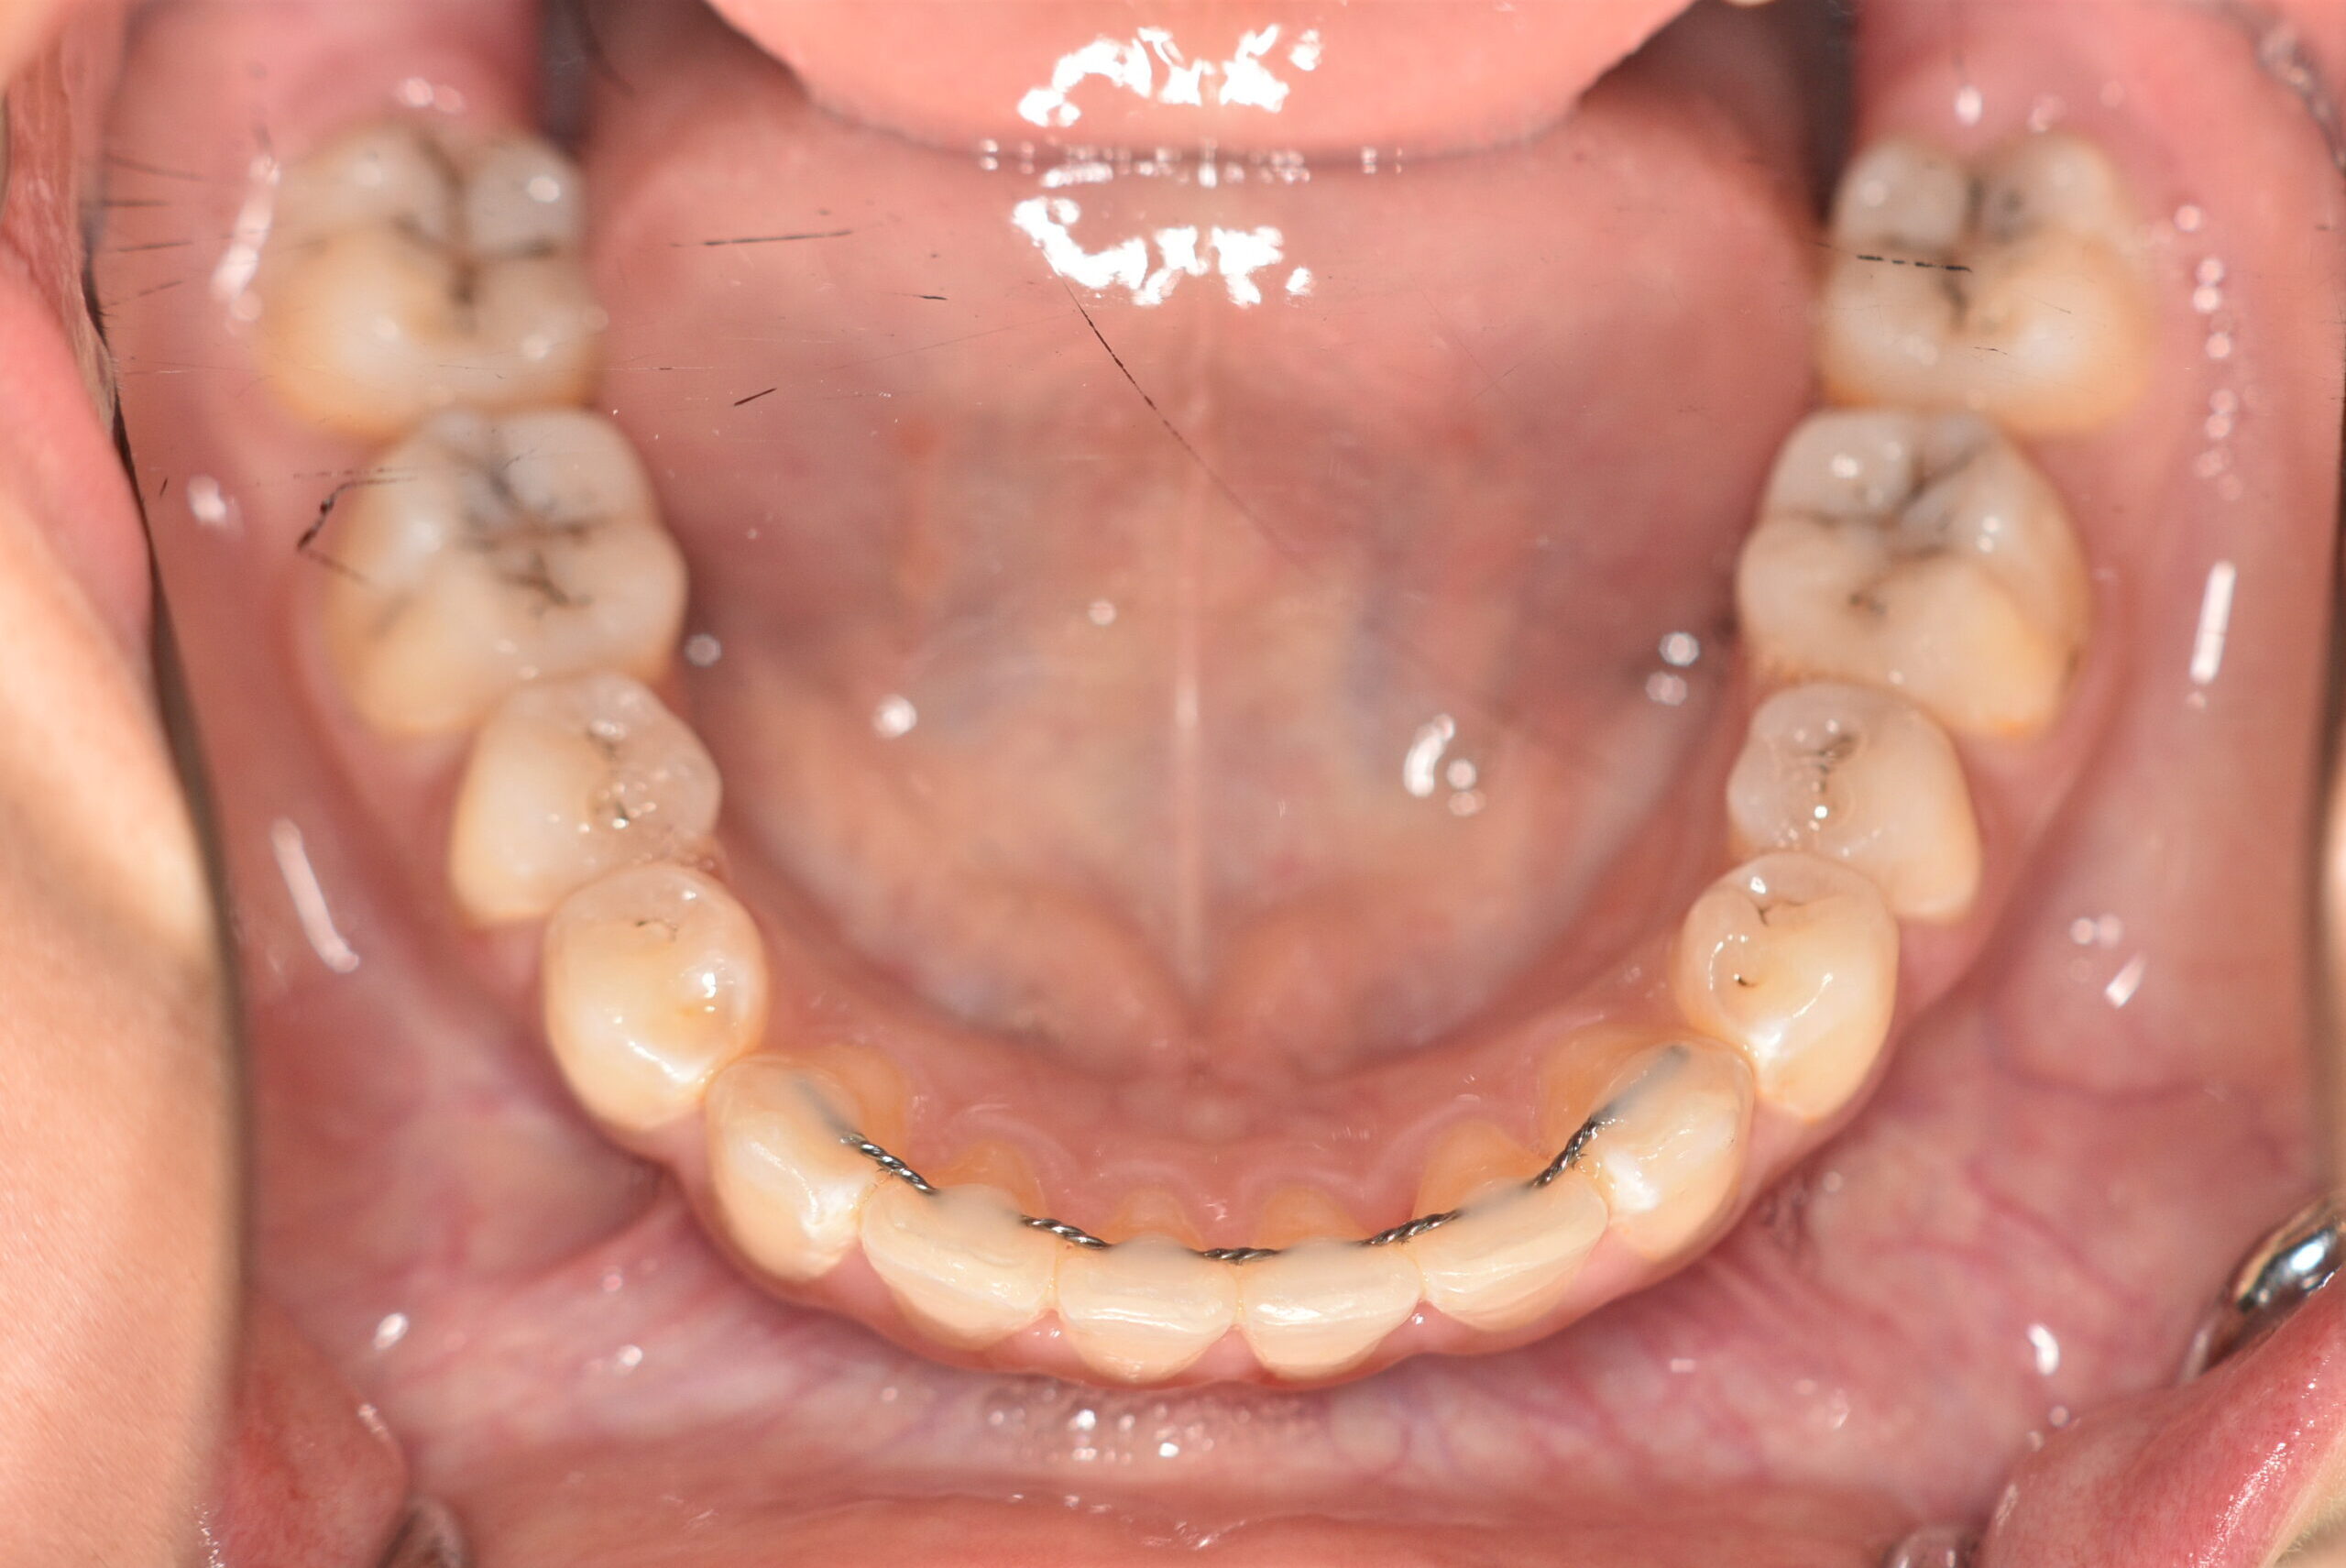

| 治療内容の詳細 | 初診時12歳の女性で、歯並びが悪く歯が磨きにくいことを気にされ来院されました。 検査の結果、上顎前突及び上下顎前歯部叢生を伴うアングルⅡ級1類不正咬合と診断しました。 治療としては、上顎左右第1小臼歯を抜歯し、セルフライゲーションブラケット装置(デーモンシステム)で歯の配列を行いました。 同時に顎間ゴムにて咬合関係の改善を行いました。 治療期間は、2年6ヶ月でした。 |